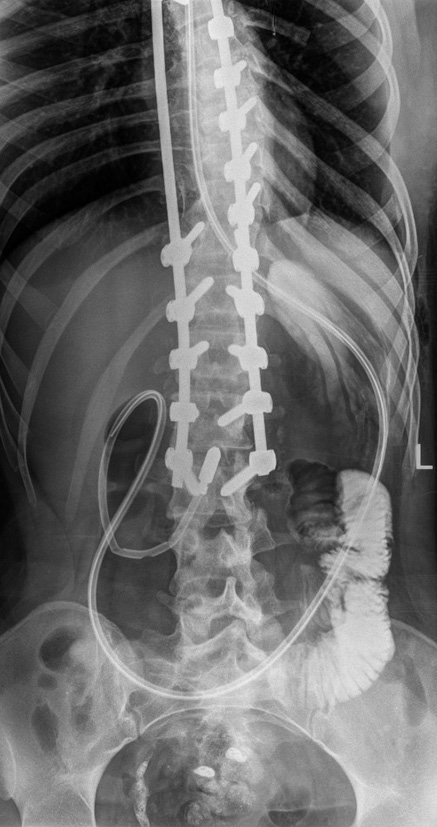

An X-ray examination of the abdominal organs with oral administration of a contrast agent was performed (Fig. 3), which revealed large curvature of the stomach in the upper border of the small pelvis, paresis, and moderate gastric dilatation. No signs of intestinal obstruction were found. An ultrasound examination of the abdominal organs showed no signs of acute surgical pathology.

Fig. 3. Radiograph of abdominal organs with oral administration of a contrast agent

Therapy of paresis and acute gastric dilatation was started, including gastric decompression (nasogastric tube), infusion therapy with electrolyte administration and partial parenteral nutrition, antiemetics (metoclopramide, ondansetron), prokinetics (ipidacrine), prolonged epidural blockade, cleansing enemas, and symptomatic therapy.